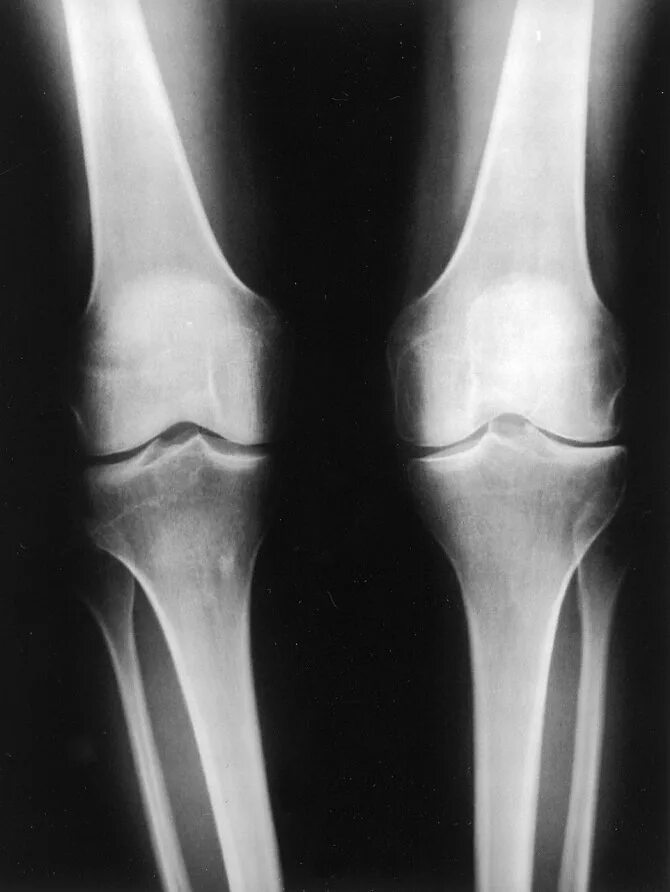

Деформирующий остеоартроз коленного сустава 1